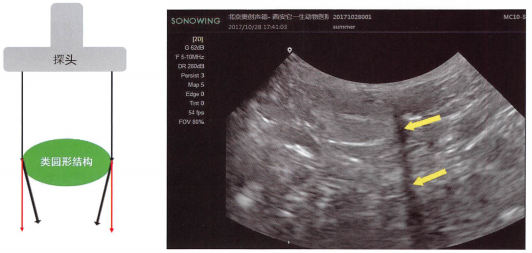

f,侧边声影:膀胱,卵巢,肠套叠,尿道等圆形结构的侧边出现声影。请翻看相关章节的图像。着重理解:圆形结构的侧边声波发生了特殊折射,产生声影。另外本书封面第3张图套叠肠管两边有侧边声影。